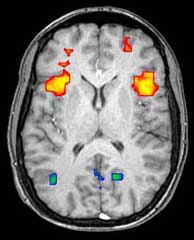

Neuroimaging

This article is about imaging. For imagery and creating maps, see Brain mapping and Outline of brain mapping.

Neuroimaging or brain imaging is the use of various techniques to either directly or indirectly image the structure, function/pharmacology of the nervous system. It is a relatively new discipline within medicine, neuroscience, and psychology.[1] Physicians who specialize in the performance and interpretation of neuroimaging in the clinical setting are neuroradiologists.

Functional imaging enables, for example, the processing of information by centers in the brain to be visualized directly. Such processing causes the involved area of the brain to increase metabolism and "light up" on the scan. One of the more controversial uses of neuroimaging has been research into "thought identification" or mind-reading.